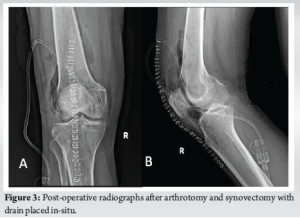

An initial aspiration of approximately 30 mL of synovial fluid was performed from the right knee on the day of presentation, which led to slight symptomatic relief. The aspirate was sent for culture and sensitivity testing, which after 48 h revealed S. marcescens, sensitive to amikacin and select carbapenem antibiotics. The patient was initiated on intravenous amikacin 500 mg twice daily and oral Faropenem 200 mg twice daily. Given the presence of a central venous catheter inserted at an outside hospital, which was suspected to be a potential source of infection, it was removed and replaced with a new central line under sterile conditions in the operating theatre. The patient initially showed clinical improvement and was discharged. However, 1 week later, he returned with a recurrence of the right knee swelling and symptoms similar to his initial presentation. He was taken to the operating theatre, where approximately 20 mL of purulent fluid was aspirated from the knee and 1 mL from the hip joint (Fig. 2). Both samples were sent for repeat culture and sensitivity testing. While the hip aspirate was sterile, the knee aspirate again showed heavy growth of S. marcescens. Notably, the minimum inhibitory concentration for amikacin had increased, indicating emerging resistance. Consequently, amikacin was discontinued. The patient subsequently underwent right knee arthrotomy with synovectomy and extensive joint lavage using 5 L of saline. A surgical drain was placed and intraoperative tissue and synovial fluid samples were sent for culture and sensitivity. Post-operative radiographs did not show any obvious abnormalities (Fig. 3). Intravenous meropenem 1 g twice daily was initiated and continued based on the updated sensitivity profile (Table 1) and continued for 6 weeks.